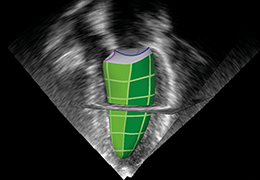

Performs 3D reconstruction and volume rendering.

Multi-planar slicing.